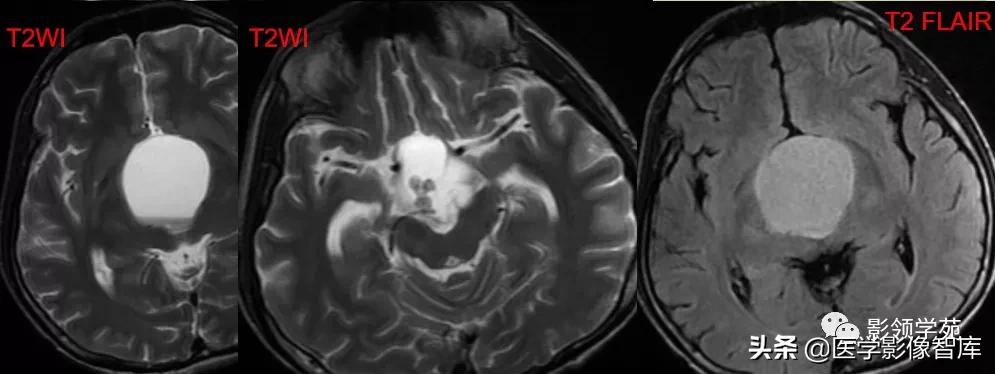

鞍区占位肿块,呈等T1等T2信号,信号均匀,边界清楚。

病灶呈均匀、显著强化(馒头样),以宽基底与前颅窝底相连,

冠状位和矢状位见脑(硬)膜尾征;

肿块突入鞍上池,向上推压视交叉,后缘紧邻垂体柄,与双侧颈内动脉相邻。